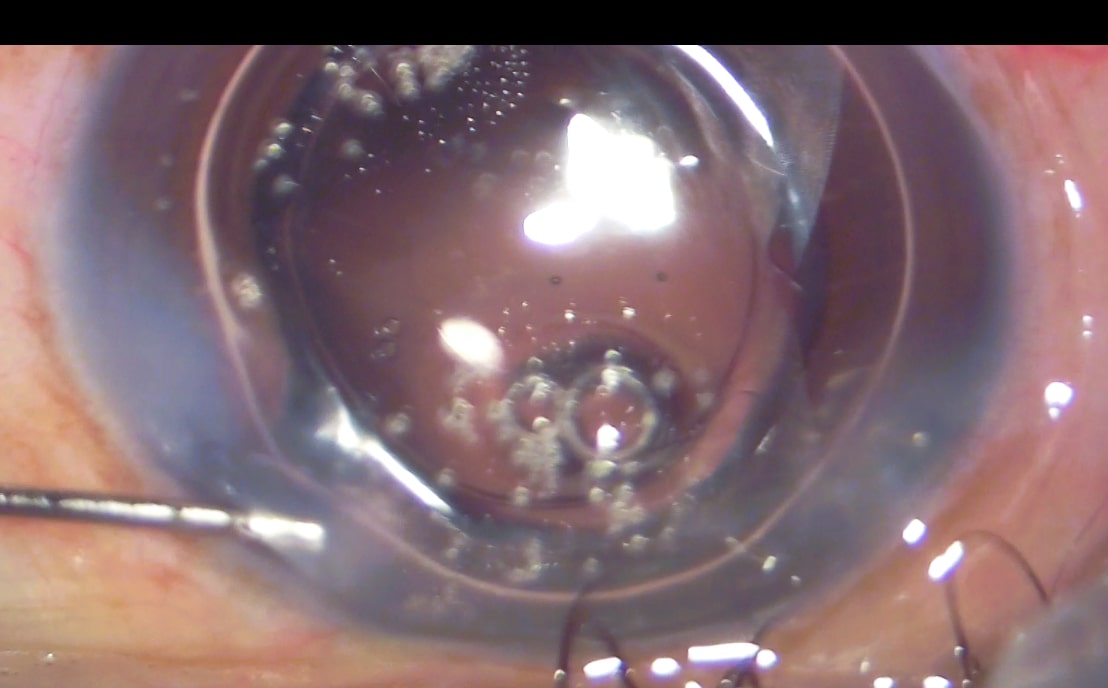

This image depicts hydrosealing/stromal hydration of the main CCI at the end of surgery using stainless-steel, flat-tipped, J-shaped, 27-G cannula at the sclero-corneal junction of the wound.